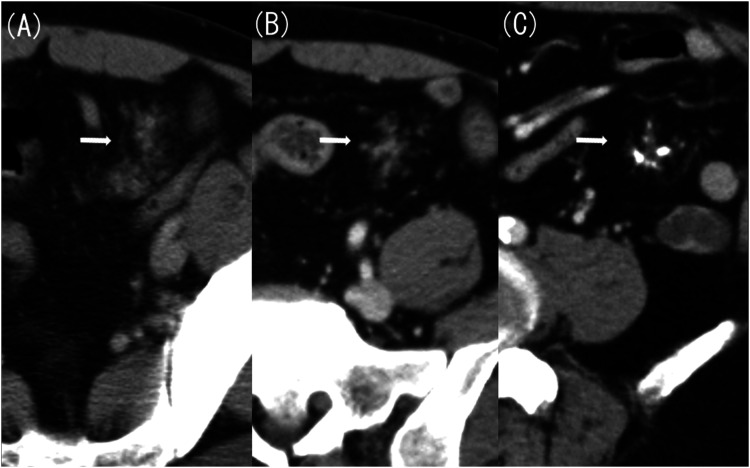

Ectopic pancreas within the mesentery is rare. In this case report, a 61-year-old man with an ectopic pancreas within the jejunal mesentery for over 20 years developed chronic pancreatitis that progressed to acute exacerbation. Our computed tomography (CT) performed for acute abdomen assessment suggested acute appendicitis or Meckel's diverticulitis. However, a CT scan taken 20 years ago revealed a structure indicative of an ectopic pancreas in the mesentery, and further imaging findings taken 10 and 4 years ago confirmed progression to chronic pancreatitis. Furthermore, we found a pancreatic stone confined in the luminal structure that corresponded to the main pancreatic duct; this stone eventually caused acute exacerbation. In summary, we report a case of mesenteric ectopic pancreas that showed typical findings of progression and acute exacerbation of chronic pancreatitis on CT.